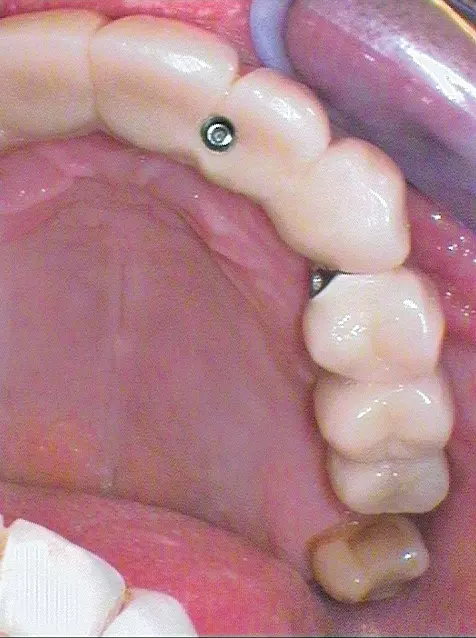

Operationsprotokoll III – Juni 2019

Nach Freilegung der Implantate regio 026,027 im Februar 2020, bei der auch die Implantation regio 037 (T3, Zimmer Biomet Dental, 4,0 mm x 13,0 mm) vorgenommen wurde (Abb. 32 OPG nach Freilegung), erfolgte im März nach Abformung mit offenem Löffel (open tray technique) und Gesichtsbogenregistrat die prothetische Versorgung mittels CAD/CAM gefräster Abutments (Dentaltechnik Hessel und Lutgen, Trier) und transversal verschraubter, verblockter VMK-Kronen (Abb. 33-36). Die Freilegung und Versorgung des Implantates 037 ist zusammen mit der Entfernung des Zahnes 38 für Juli 2020 geplant.